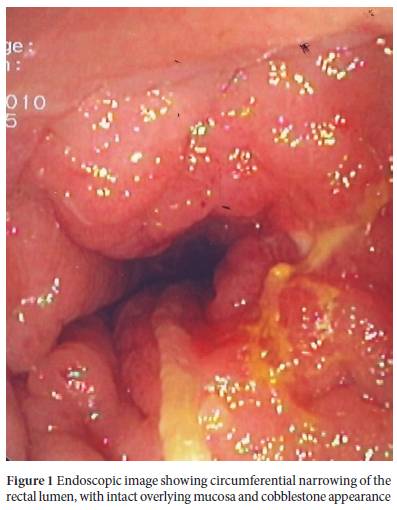

Case Report Primary Hodgkin’s Lymphoma Of The Rectum: An ...

Primary Hodgkin’s Lymphoma of the Rectum: An Unusual Presentation Introduction Hodgkin’slymphoma(HL)isamalignantclonalproliferationof B-cell origin characterized by the presence of Reed-Sternberg cells or ... Return Doc